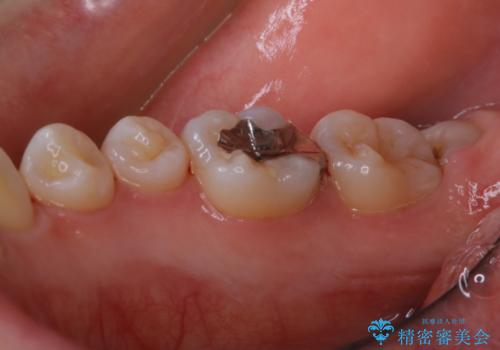

一か所茶色く色が残っている所がありますが、これは詰め物の変色です。

以前にCR(コンポジットレジン)による虫歯の治療での充填がされています。

CRは経年的に劣化や変色、着色がついてしまいます。

PMTCでしっかりとクリーニングを行うと、古いCRが目立つことがあり、気になる際は詰め替えを行います。